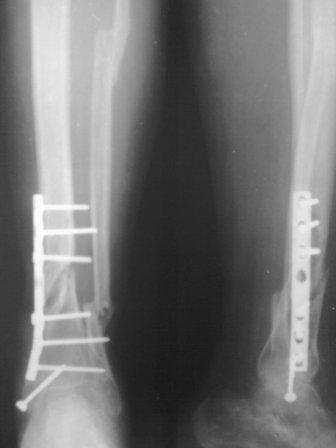

Вчера отправил фото, почему-то не вышел.

Отправляю фото повторно.

Состояние раны ч-з две недели, покрыт корочкой, подним идет хорошая грануляция, повязка только димексид с фурациллином, пока нагноения нет, выделения из раны нет, 5 дней уже антибиотиков не принимает. Фото и рентген прилагается.

Как Джолдас предлагал спицы удалены, в дистальном кольце три спицы, рекомедована дозированная нагрузка, и больной выпысан. приедит ч-з две нед.